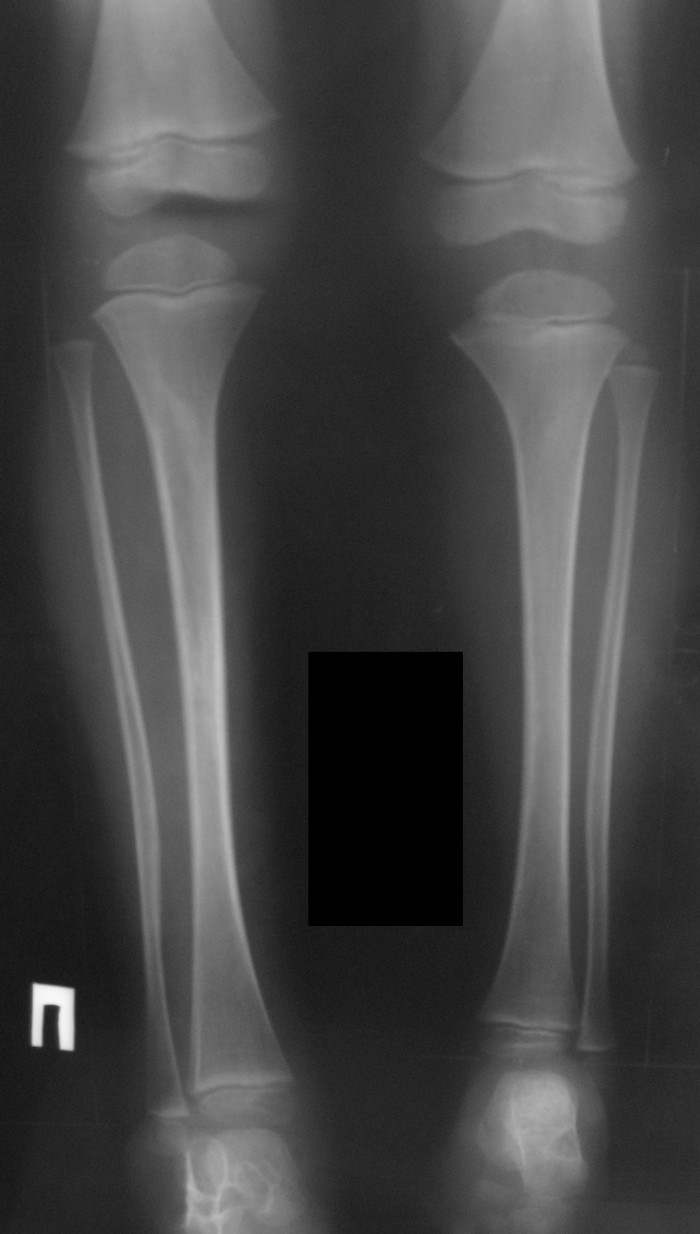

Спасибо, уважаемые коллеги, за комментарии. Взвесили все "за и против" и

остановились на эпифизеодезе. Теперь будем ждать результатов.